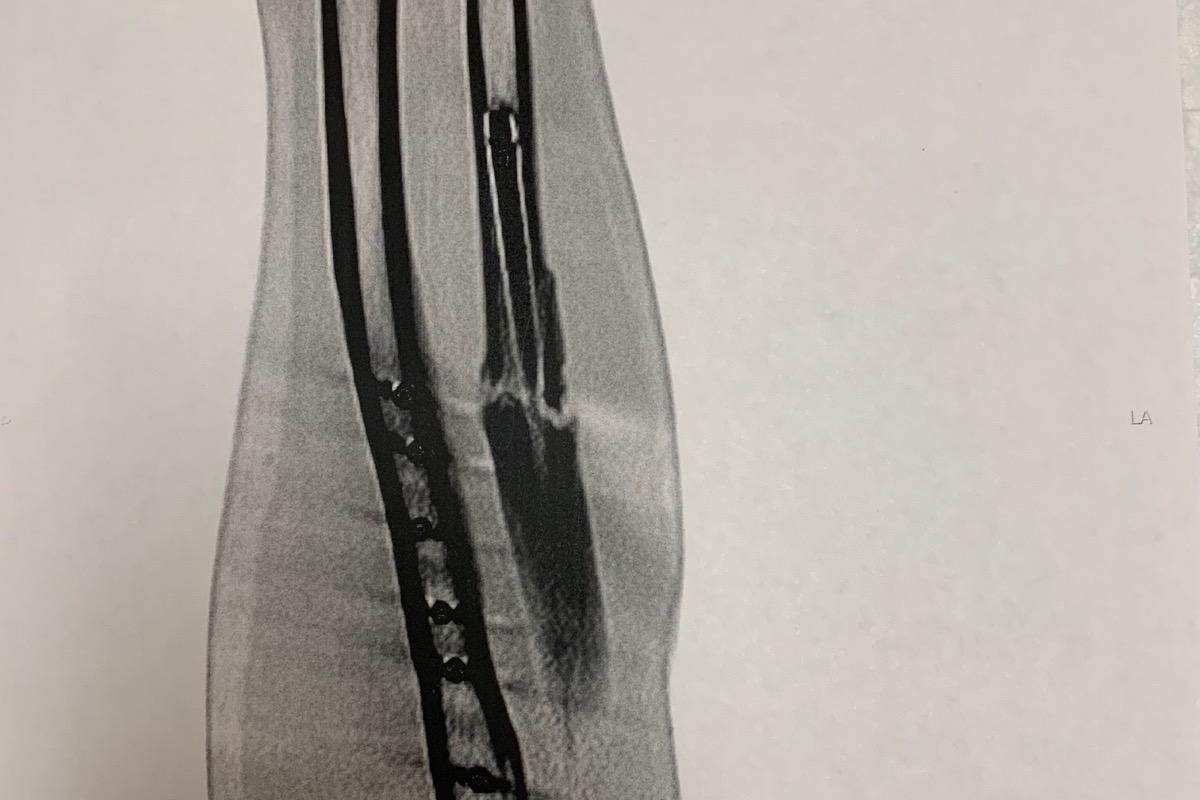

Now fast forward to June and I find out one of the bones in my arm (ulnar) did not heal and I had to undergo another surgery to repair the broken bone. The most recent surgery required removal of some of the hardware in my arm, and replacing it with a bone graft from my hip and new metal hardware to restart the healing process. This also required taking a few weeks off of work to recover. I now have two plates and 14 screws in my arm and have had hundreds of staples and stitches during the surgeries and am still trying to fully recover so that I can get cleared for full work status.

(The bone break is very clear on the right, 9 months later)

(The bone break is very clear on the right, 9 months later)

(Amazing sister that helped me out! Took her out for dinner before she had to fly home)Now fast forward to June and I find out one of the bones in my arm (ulnar) did not heal and I had to undergo another surgery to repair the broken bone. The most recent surgery required removal of some of the hardware in my arm, and replacing it with a bone graft from my hip and new metal hardware to restart the healing process. This also required taking a few weeks off of work to recover. I now have two plates and 14 screws in my arm and have had hundreds of staples and stitches during the surgeries and am still trying to fully recover so that I can get cleared for full work status.

(The bone break is very clear on the right, 9 months later)

(The bone break is very clear on the right, 9 months later) Now normally when you are in an accident the other persons insurance would cover these bills. But, you are not required to have insurance on a jetski, and when the person that hit you has nothing, there is nothing to go after. He gets to walk away from the incident with no injuries and not having to take responsibility for what he did. The police did not even issue any citation for it, even when there were plenty of witnesses.